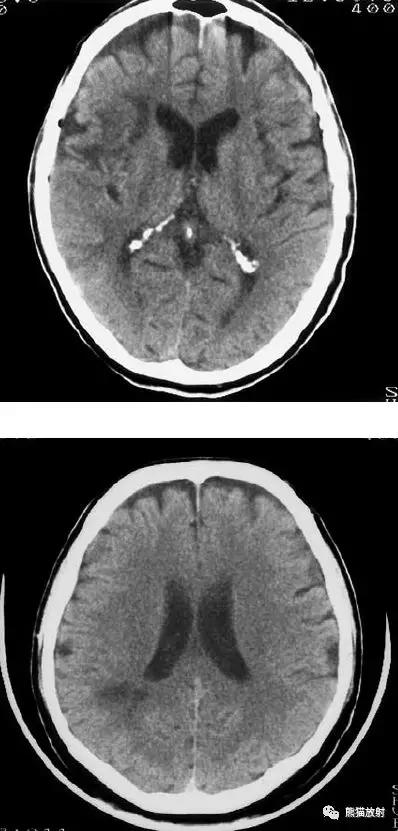

右侧豆状核梗死灶(发病后15d),明显均匀强化。另左侧丘脑见腔隙性梗死灶。